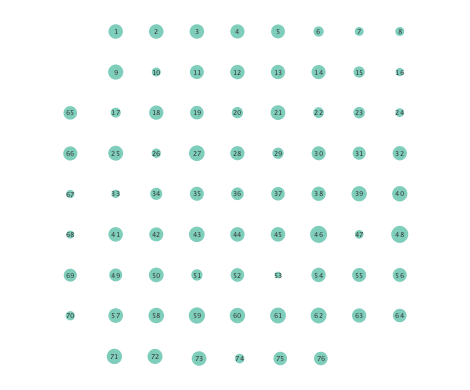

Figure 2 depicts networks inferred from different algorithms for both preictal and ictal intervals of the time series. The figure illustrates results obtained by the linear SVARM, and the K-SVARM approach with and without kernel selection. Each node in the network is representative of an electrode, and it is depicted as a circle, while the node arrangement is forced to remain consistent across the four visual representations. A cursory inspection of the visual maps reveals significant variations in connectivity patterns between ictal and preictal intervals for both models. Specifically, networks inferred via the K-SVARMs, reveal a global decrease in the number of links emanating from each node, while those inferred via the linear model depict increases and decreases in links connected to different nodes. Interestingly, the K-SVARM with kernel selection recovered most of the edges inferred by the linear and the K-SVARM using a polynomial kernel, which implies that both linear and nonlinear interactions may exist in brain networks. Clearly, one is unlikely to gain much insight only by visual inspection of the network topologies. To further analyze differences between inferred networks from both models, and to assess the potential benefits gained by adopting the novel scheme, several network topology metrics are computed and compared in the next subsection.

First, in- and out-degree was computed for nodes in each of the inferred networks. Note that the in-degree of a node counts its number of incoming edges, while the out-degree counts the number of out-going edges. The total degree per node sums the in- and out-degrees, and is indicative of how well-connected a given node is. Figure 3 depicts nodes in the network and their total degrees encoded by the radii of circles associated with the nodes. As expected from the previous subsection, Figures 3 (a) and (b) demonstrate that the linear SVARM yields both increases and deceases in the inferred node degree. On the other hand, the nonlinear SVARM leads to a more spatially consistent observation with most nodes exhibiting a smaller degree after the onset of a seizure (see Figures 3 (c) and (d)), which may imply that causal dependencies thin out between regions of the brain once a seizure starts.